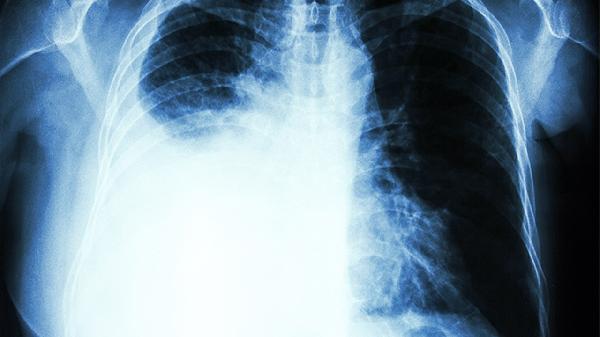

左肺下叶索条是什么意思

左肺下叶索条通常是指影像学检查中发现的左肺下叶条索状阴影,可能与肺部炎症、结核、纤维化等病变有关。建议结合临床症状和其他检查进一步明确诊断。 左肺下叶索条在影像学上表现为细长、线状的密度增高影,多数

阳过后肺结节会消失吗

阳过后肺结节可能会消失。新冠病毒感染与呼吸道症状和肺部影像学改变有关,但与肺结节的关系不明确。肺结节是肺部影像学上的小圆形,一般直径<3cm,可能是多种疾病或情况的结果。 如果新冠病毒感染后,进行胸

胸腔积液血胸必定是肺癌吗

胸腔积液、血胸不一定是肺癌。引起上述症状的原因较多,除肺癌外,还可能是肺部感染性疾病、结核性胸膜炎等疾病导致。 一、不是肺癌的情况 1.肺部感染性疾病:如肺炎链球菌肺炎、金黄色葡萄球菌肺炎、病毒性

血胸会影响生命吗 细说血胸引发的各种影响

血胸可能影响生命,具体取决于出血量和速度。血胸是指血液积聚在胸膜腔内,可能由外伤、手术并发症或凝血功能障碍等原因引起。 少量血胸通常不会立即威胁生命,患者可能仅表现为轻度胸闷、呼吸急促或局部疼痛。此